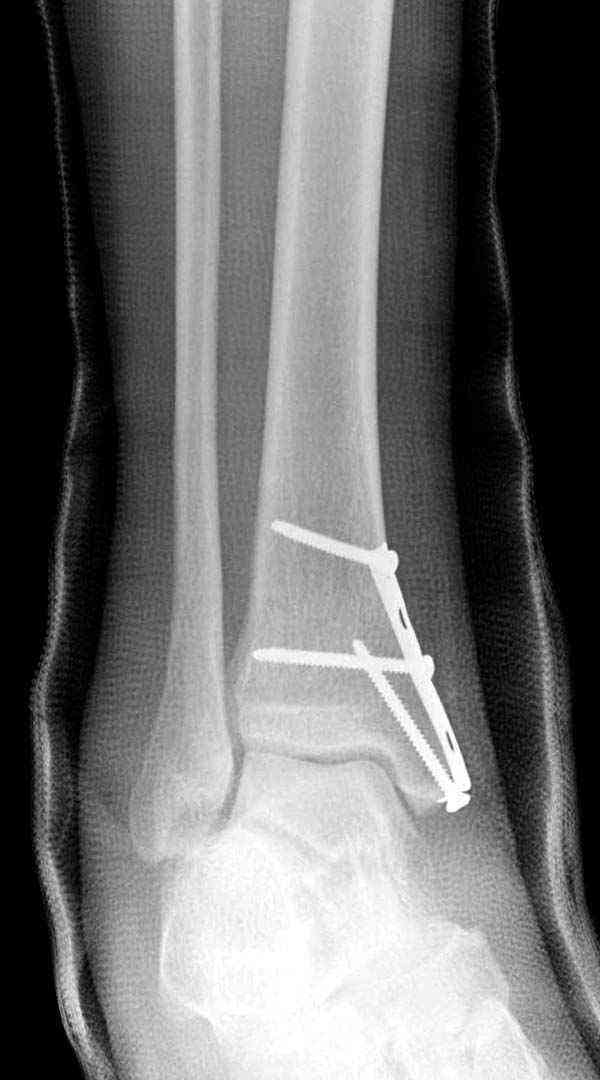

Случай прошлого года:пациентка-молодая ,крупная женщина ,30лет.Травма в начале апреля 2009г-пронационный перелом лодыжек с подвывихом стопы.Ко мне обратилась через 35 дней,прооперирована 22.05.2009г.Внутренняя лодыжка фиксирована по Веберу,наружная реконструктивной пластиной с наложением болта-стяжки.Иммобилизация "сапожок" в течении месяца,затем пригипсовано "стремя".Гипс снят 10.07.2009г

Достаточно быстрое восстановление функции.В октябре 2009г-почувствовала боль,в области рубца над гайкой открылся свищ.На Р-граммах-консолидация переломов и смещение гайки по стяжке.10.11.2009г-конструкции удалены,санация,заживление ран.В настоящее время пациентку ничего не беспокоит.На операции-раскручивание гайки-болталась на конце стяжки.Вопросы:какой механизм раскручивания и что я неправильно сделал?Свои версии:1)в области синдесмоза успела образоваться рубцовая ткань,которая при движении в суставе"пружинила",поскольку голеностопный сустав является спиральным, то и биомеханика подобна кривошипному механизму.2)Реконструктивная пластина не "реконструировалась" по форме лодыжки.Наложил,как есть.То есть подпружинивала сама пластина.Ну,это мои догадки.Что нужно,чтобы избегать впредь таких,пусть и не "страшных"осложнений:Рассверливать через лодыжку область синдесмоза?Ставить шайбу-гровер?Тщательно моделировать пластину?Прилагаю сравнительные снимки-сразу после операции и перед удалением конструкции.

Визуально никаких вопросов по репозиции не было.Да и на основании чего сомнения,что наружная лодыжка не полностью репонирована или прорезалась проволка ???Я не вижу...Снимок после репозиции справа.